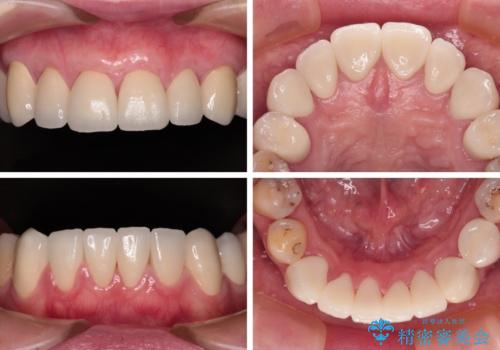

むし歯だらけの前歯をオールセラミッククラウンできれいに

全顎的にむし歯が多く、根管治療の必要奥歯や、審美的に気になっている前歯を中心にオールセラミッククラウンにて補綴治療を行うこととしました。

上顎前歯は歯肉退縮により歯根が露出していたため、事前に歯肉移植術により根面被覆を行い、その後にオールセラミッククラウンを装着することとしました。

歯肉移植術による根面被覆を行うかどうかは非常に悩まれていましたが、歯肉が覆われたことで長く見えていた歯の長さが整い、きれいな前歯の仕上がりとなりました。